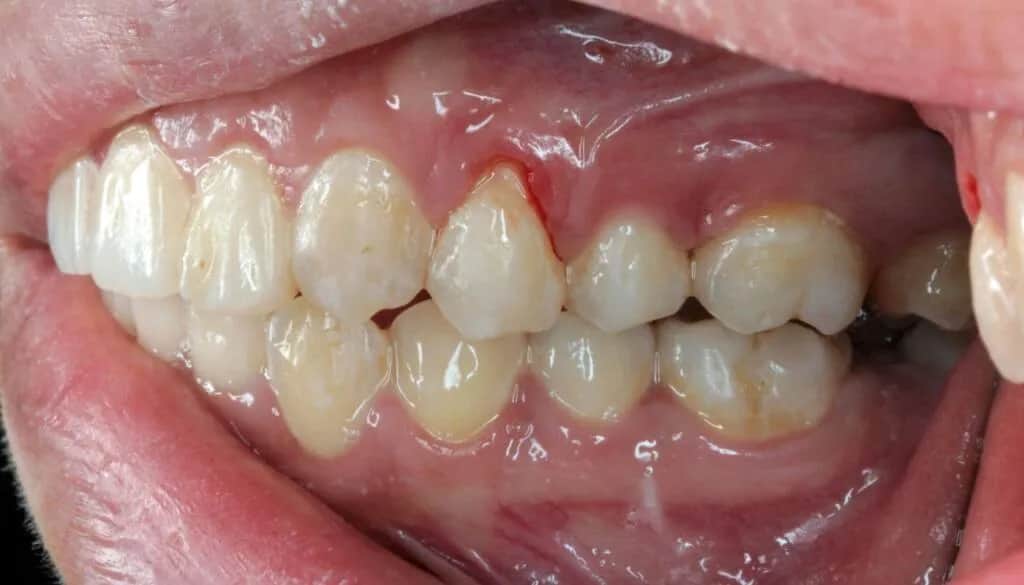

- Widoczne wydłużenie koron zębów: Zęby zaczynają wyglądać na dłuższe niż wcześniej, a linia dziąseł wyraźnie się obniża. To sygnał, że tkanka dziąsłowa uległa cofnięciu.

Niestety, nie zawsze recesja dziąseł jest wynikiem naszych błędów. Czasem problem tkwi znacznie głębiej, w czynnikach, na które mamy mniejszy wpływ. Jednym z głównych winowajców są choroby przyzębia, zwłaszcza paradontoza. To zaawansowane zapalenie dziąseł prowadzi do niszczenia tkanek utrzymujących ząb w kości, co skutkuje nie tylko cofaniem się dziąsła, ale także zanikiem kości. Recesja jest więc często jednym z kluczowych objawów tej poważnej choroby. Ponadto, nie można ignorować predyspozycji genetycznych. Osoby z tzw. cienkim biotypem dziąsła, czyli naturalnie delikatną i cienką tkanką dziąsłową, są znacznie bardziej narażone na recesje, nawet przy wzorowej higienie. Do tego dochodzą wady zgryzu i nieprawidłowe ustawienie zębów. Zęby, które są stłoczone, wychylone lub obrócone, mogą być narażone na nadmierne obciążenia mechaniczne, co sprzyja cofaniu się dziąseł w tych konkretnych obszarach.